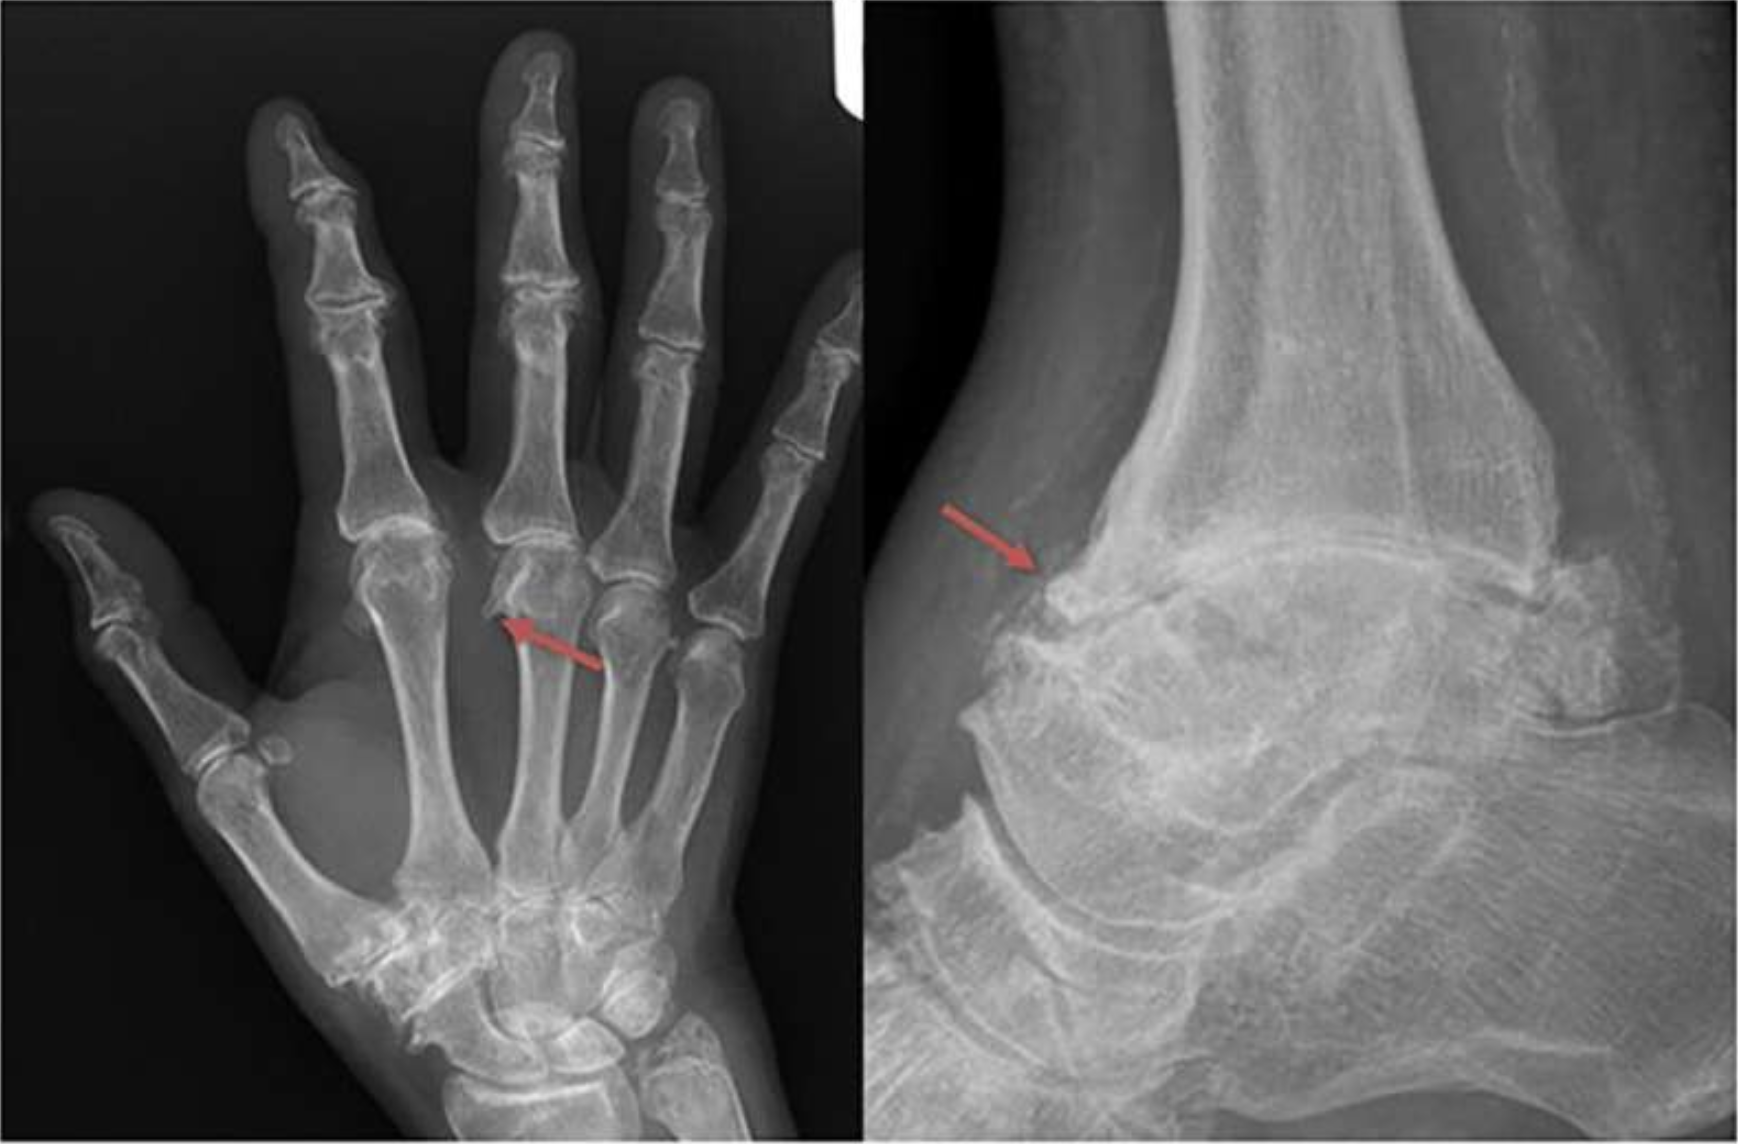

Haemochromatosis arthropathy is a complication associated with haemochromatosis that most commonly affects the joints of the hands, but also the knees, ankles, and hips. Despite its impact, it has long lacked a formal classification. The European Alliance of Associations for Rheumatology (EULAR) task force has now developed the first classification criteria for haemochromatosis arthropathy, which were presented by Prof. Patrick Kiely during the EULAR Congress held in Barcelona on 14 June 2025. A score of 5 out of 11 effectively distinguishes haemochromatosis arthropathy from similar conditions such as osteoarthritis and calcium pyrophosphate deposition disease (CPPD), with high specificity. These criteria will support future research and improve recognition of this condition. The criteria are summarised in the following table.